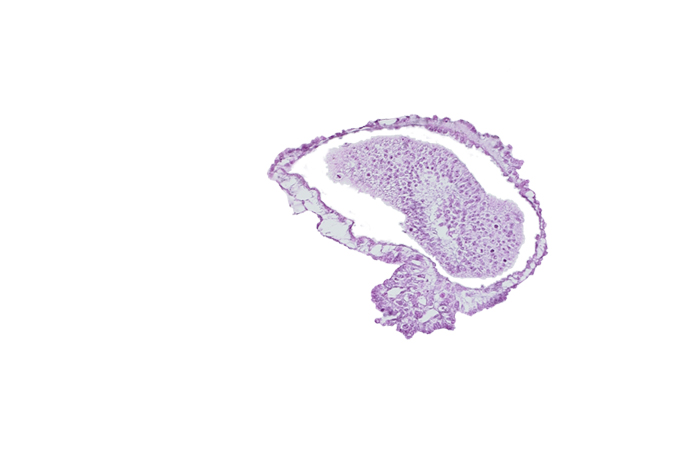

Carnegie Embryo #10157 | Location: 09-03

Keywords: allantoic diverticulum in connecting stalk, amniotic cavity, caudal eminence, gastrulation (primitive) groove

Source: The Virtual Human Embryo.